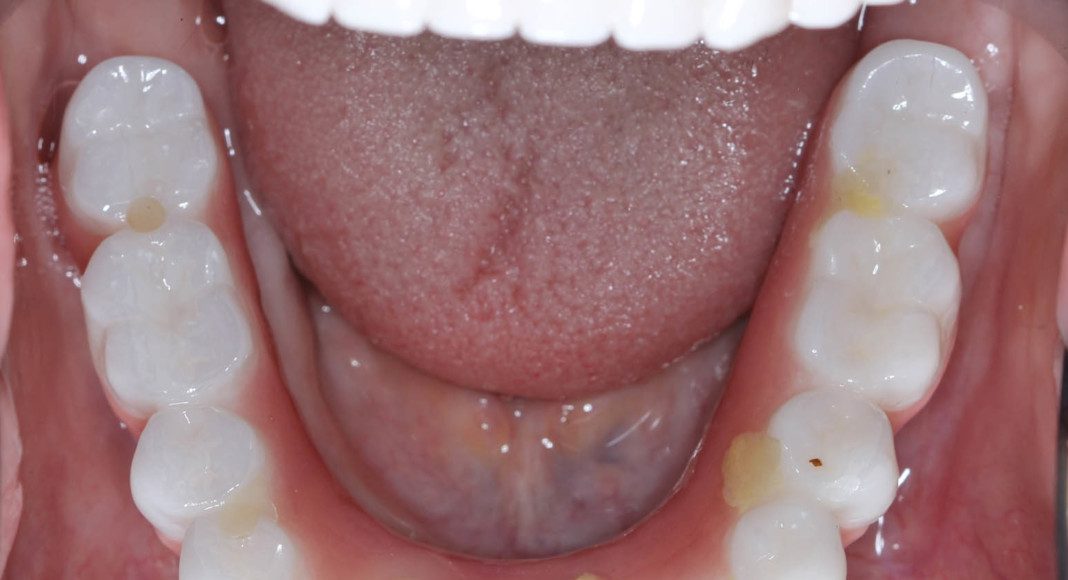

Lower zirconia bridge, off the master cast. This is the intaglio (tissue side) of the prosthesis. Note that is flat to convex for easy cleaning.

Right lateral, mirror view of the upper and lower zirconia bridges. Note the beautiful, healthy tissue response.